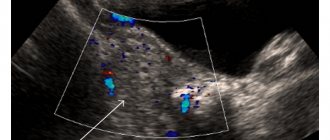

When performing an ultrasound, the cyst is easy to detect. It is visualized as a rounded anechoic formation with a homogeneous structure. It has a clearly defined capsule. Cysts differ in their internal structure. Ultrasound may reveal:

- anechoic homogeneous formation;

- anechoic structure of irregular shape with partitions inside;

- homogeneous anechoic formations with smooth or mesh wall structures;

- tumors, inside of which there is a parietal mid-echoic area, this is how blood clots inside the cyst are visualized.

If it is difficult to establish a diagnosis based on the results of an ultrasound, then color Doppler sonography may be prescribed. This examination allows you to distinguish a tumor from a cyst. Blood flow is preserved in ovarian tumors, but it is absent in luteal cystic neoplasms.

- For a reliable diagnosis, ultrasound is prescribed. A cavity of up to 8 centimeters with fluid inside is visualized on the ovary.

- Doppler examination. It is used to evaluate blood flow. In luteal cysts there is no blood flow, while in tumor formations it is detected.

In phase 2 of the cycle, the diameter of the standard corpus luteum should be 18-27 mm. If an anechoic structure with a diameter of more than 30-35 mm is detected on ultrasound, it is diagnosed that a cyst has formed in place of the corpus luteum. Its main difference is that it is anechoic; it does not transmit ultrasonic waves and appears on the screen as a dark spot.